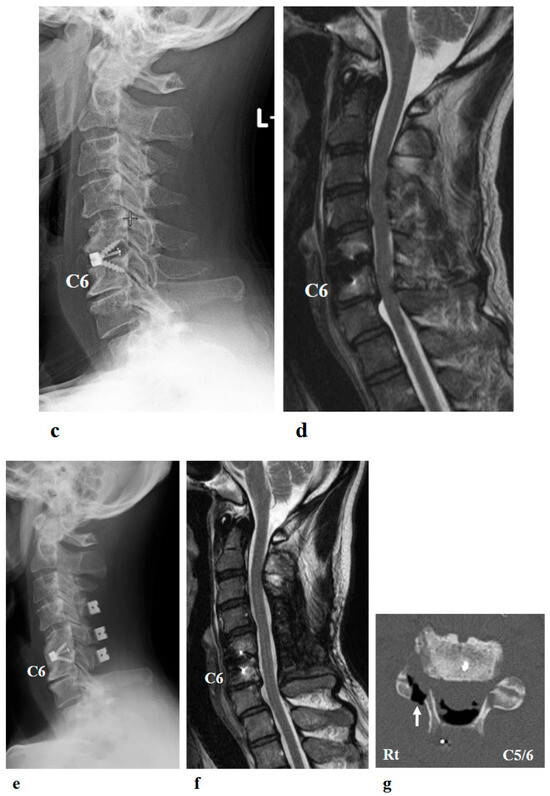

Figure 8.

Right shoulder T1 and T2-weighted magnetic resonance imaging showed atrophy and fatty infiltration of several musculus, including supraspinatus, deltoideus, and subscapularis (arrow) on coronal (a) and sagittal (b).

Right shoulder T1- and T2-weighted MRI before intervention showed atrophy and fatty infiltration of several musculus, including supraspinatus, deltoideus, and subscapularis on sagittal and coronal. Following 8 months and 14 months started HAL training. MRI showed no change in atrophy and fatty infiltration of the supraspinatus, deltoideus, and subscapularis. This assessment was backed by a radiologist (Figure 8).

Interestingly, despite the patient’s functional improvements in ROM and muscle strength, serial MRI assessments performed at 8 and 14 months after the initiation of HAL therapy demonstrated no appreciable reversal of atrophy or fatty infiltration in the supraspinatus, deltoid, or subscapularis muscles. This finding suggests that the observed recovery was not primarily attributable to structural restoration of muscle bulk, but rather to neuromuscular mechanisms such as enhanced recruitment of residual motor units, cortical reorganization, and motor learning facilitated by interactive biofeedback training with HAL [18]. In cases of chronic peripheral neuropathy with longstanding muscle weakness (MMT grade 2 persisting for years), spontaneous recovery is generally considered limited. Therefore, the improvement observed in this patient may have resulted from hypertrophy of partially innervated muscle fibers, increased efficiency of motor unit recruitment, and central neuroplastic adaptations compensating for peripheral denervation [19]. Moreover, by providing real-time biofeedback and suppressing maladaptive compensatory patterns, HAL therapy may have facilitated more physiologic movement strategies, thereby amplifying the functional gains.